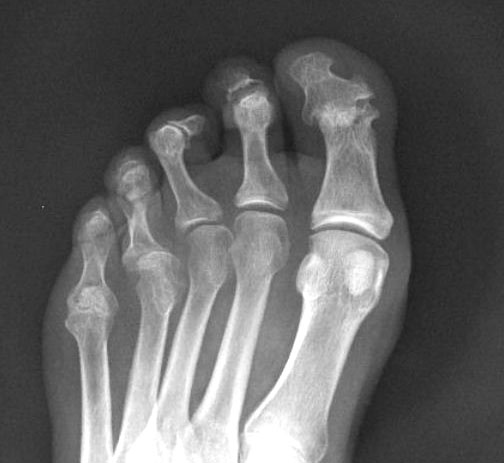

Artritis psoriásica y falange bífida.

Artritis psoriásica.